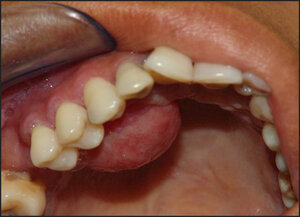

At the clinical examination, we observed a nodular-aspect lesion approximately 2 cm in diameter, painless, located in the palatine inserted gingiva near the right upper premolars, presenting a base of pediculated implantation, consistent with palpation, painless, smooth, bleeding surface when inspected, a pale pink color similar to the adjacent tissue (Figures 1 and 2).